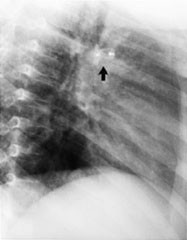

Amplatzer-proppen for lukking av ductus, som vi har benyttet siden november 1997, består av et spunnet nett av tynne nitinoltråder i en forutbestemt form (fig 3). Den har en 7 mm lang, kon kjerne og en flat, sirkulær, skiveformet brem på aortasiden på 2 – 3 mm. Proppen inneholder polyesterfibrer som skal indusere koagulering. Proppen legges gjennom en 5 eller 6 french innføringsskjede som blir ført til aorta gjennom ductus. Vi har brukt proppen til ductuser der minste diameter er ca. 3 mm eller mer. En ductus på 2,1 mm ble likevel proppet etter at en spiral først hadde dislokert flere ganger, men fordi den fortsatt var festet på innføringsvaieren, kunne den lett fjernes. Likedan ble det satt inn en propp i en ductus på 2,4 mm etter at en spiral på 5 mm hadde embolisert til venstre a. pulmonalis.